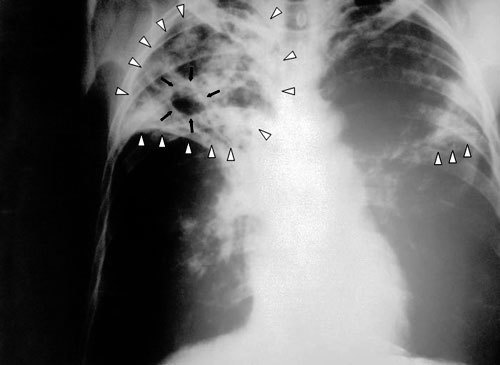

Гуманитарная организация "Международный медицинский корпус" подвела итоги работы на Северном Кавказе за 2009 год. Врачи отмечают, что в регионе растет заболеваемость туберкулезом и ВИЧ, а лечебно-профилактические учреждения в достаточном объеме отсутствуют.

Рост заболеваемости туберкулезом на Северном Кавказе практически самый высокий в России

"Рост заболеваемости туберкулезом на Северном Кавказе практически самый высокий в России. В Чечне как уже зарегистрированных, так и новых случаев больше, чем в любом другом регионе России за исключением тех, где находятся учреждения пенитенциарной системы, в частности, в некоторых регионах Сибири", - рассказал корреспонденту "Кавказского узла" руководитель российского отделения ММК Семен Расин.

По данным врачей, сегодня в Чечне около 5 000 зарегистрированных больных туберкулезом. По словам Семена Расина, официальные цифры заболеваемости отражают лишь часть реальности. "Уровень заболеваемости туберкулезом очень значительный, причем уровень его выявляемости крайне низок. Очень плохой уровень подготовки специалистов. Есть энтузиасты, которые пытаются что-то сделать. А вот квалифицированных специалистов на местах практически нет - никто не хочет ехать работать в Чечню", - сетует руководитель российского отделения ММК.

Но и это не спасает ситуацию: по подсчетам ММК, если в 2001 году в республике было зарегистрировано только три случая одновременного заражения СПИДом и туберкулезом, то в 2008 году новых случаев одновременного заражения было выявлено 47, а за 9 месяцев 2009 года - 43.

На вопрос, в чем причины роста числа людей, больных туберкулезом, Семен Расин отвечает так: "Во время войны в Чечне не было никаких лекарств вообще. Все больные, которые находились на лечении от туберкулеза, перестали его получать, заражая при этом остальных. Во-вторых, туберкулез - болезнь социальная, болезнь бедности. Уровень безработицы в Чечне достигает 70% населения, а безработица среди молодежи - 85%".